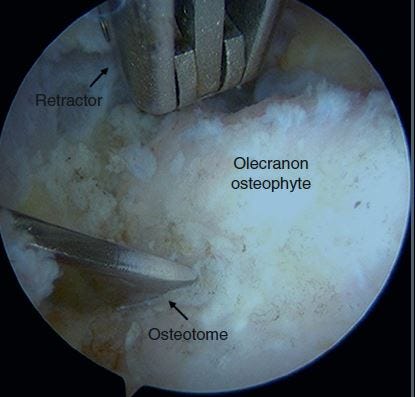

It is absolutely necessary to make an accurate diagnosis, start by knowing what to look for. Figure 2 shows the example x-rays of a bone chip. Once properly diagnosed, treatment will depend on the severity of the symptoms. Some players can get through the season with anti-inflammatory medication and even a cortisone injection. Other players will experience pain to a debilitating degree, and require surgery. Fortunately, bone chips can be removed arthroscopically, and as you can see in figures 3, 4, and 5 and the pain related to the bone chips is eliminated.